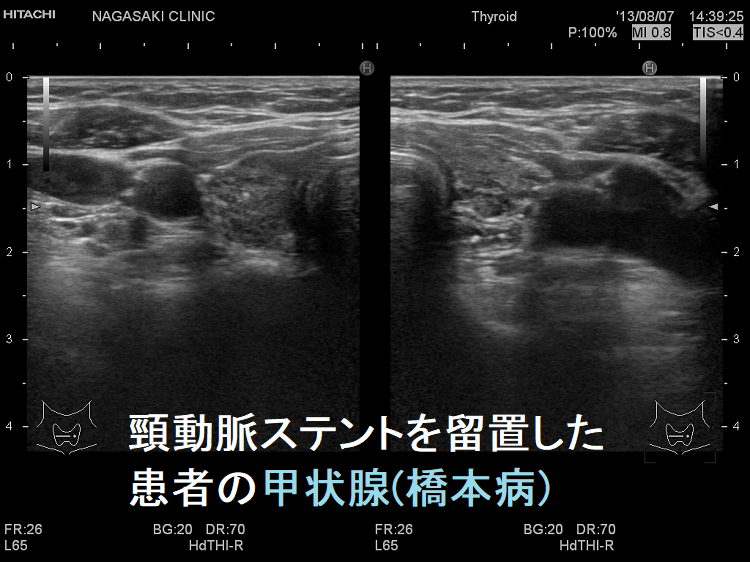

頸動脈ステントを留置した患者の甲状腺 超音波(エコー)画像;写真の頸動脈ステントを留置した患者は、甲状腺機能低下症/橋本病により動脈硬化が進行していました。(甲状腺と動脈硬化)